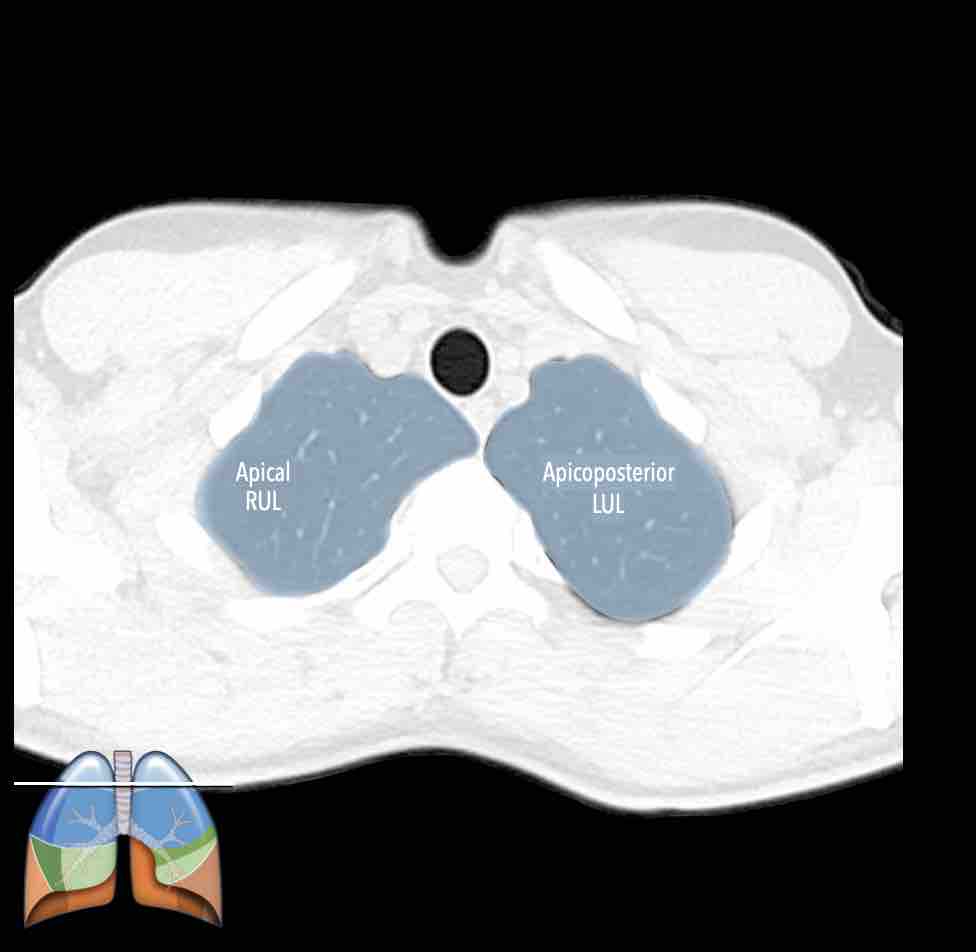

Thùy trên phổi trái (màu xanh lam)

Phân thùy đỉnh-sau (LB1/2) – Phân thùy trước (LB3)

Giải phẫu phân thùy của hai phổi có tính đối xứng nhất định, vì phổi trái chỉ khác phổi phải một chút.

Phổi phải có ba thùy (gồm thùy trên, thùy giữa và thùy dưới) với mười phân thùy,

trong khi phổi trái có hai thùy (gồm thùy trên và thùy dưới) với số phân thùy ít hơn.

Ở

thùy trên phổi trái, phân thùy đỉnh và phân thùy sau có chung một thân phế quản phân thùy

và được gộp lại thành phân thùy đỉnh-sau.